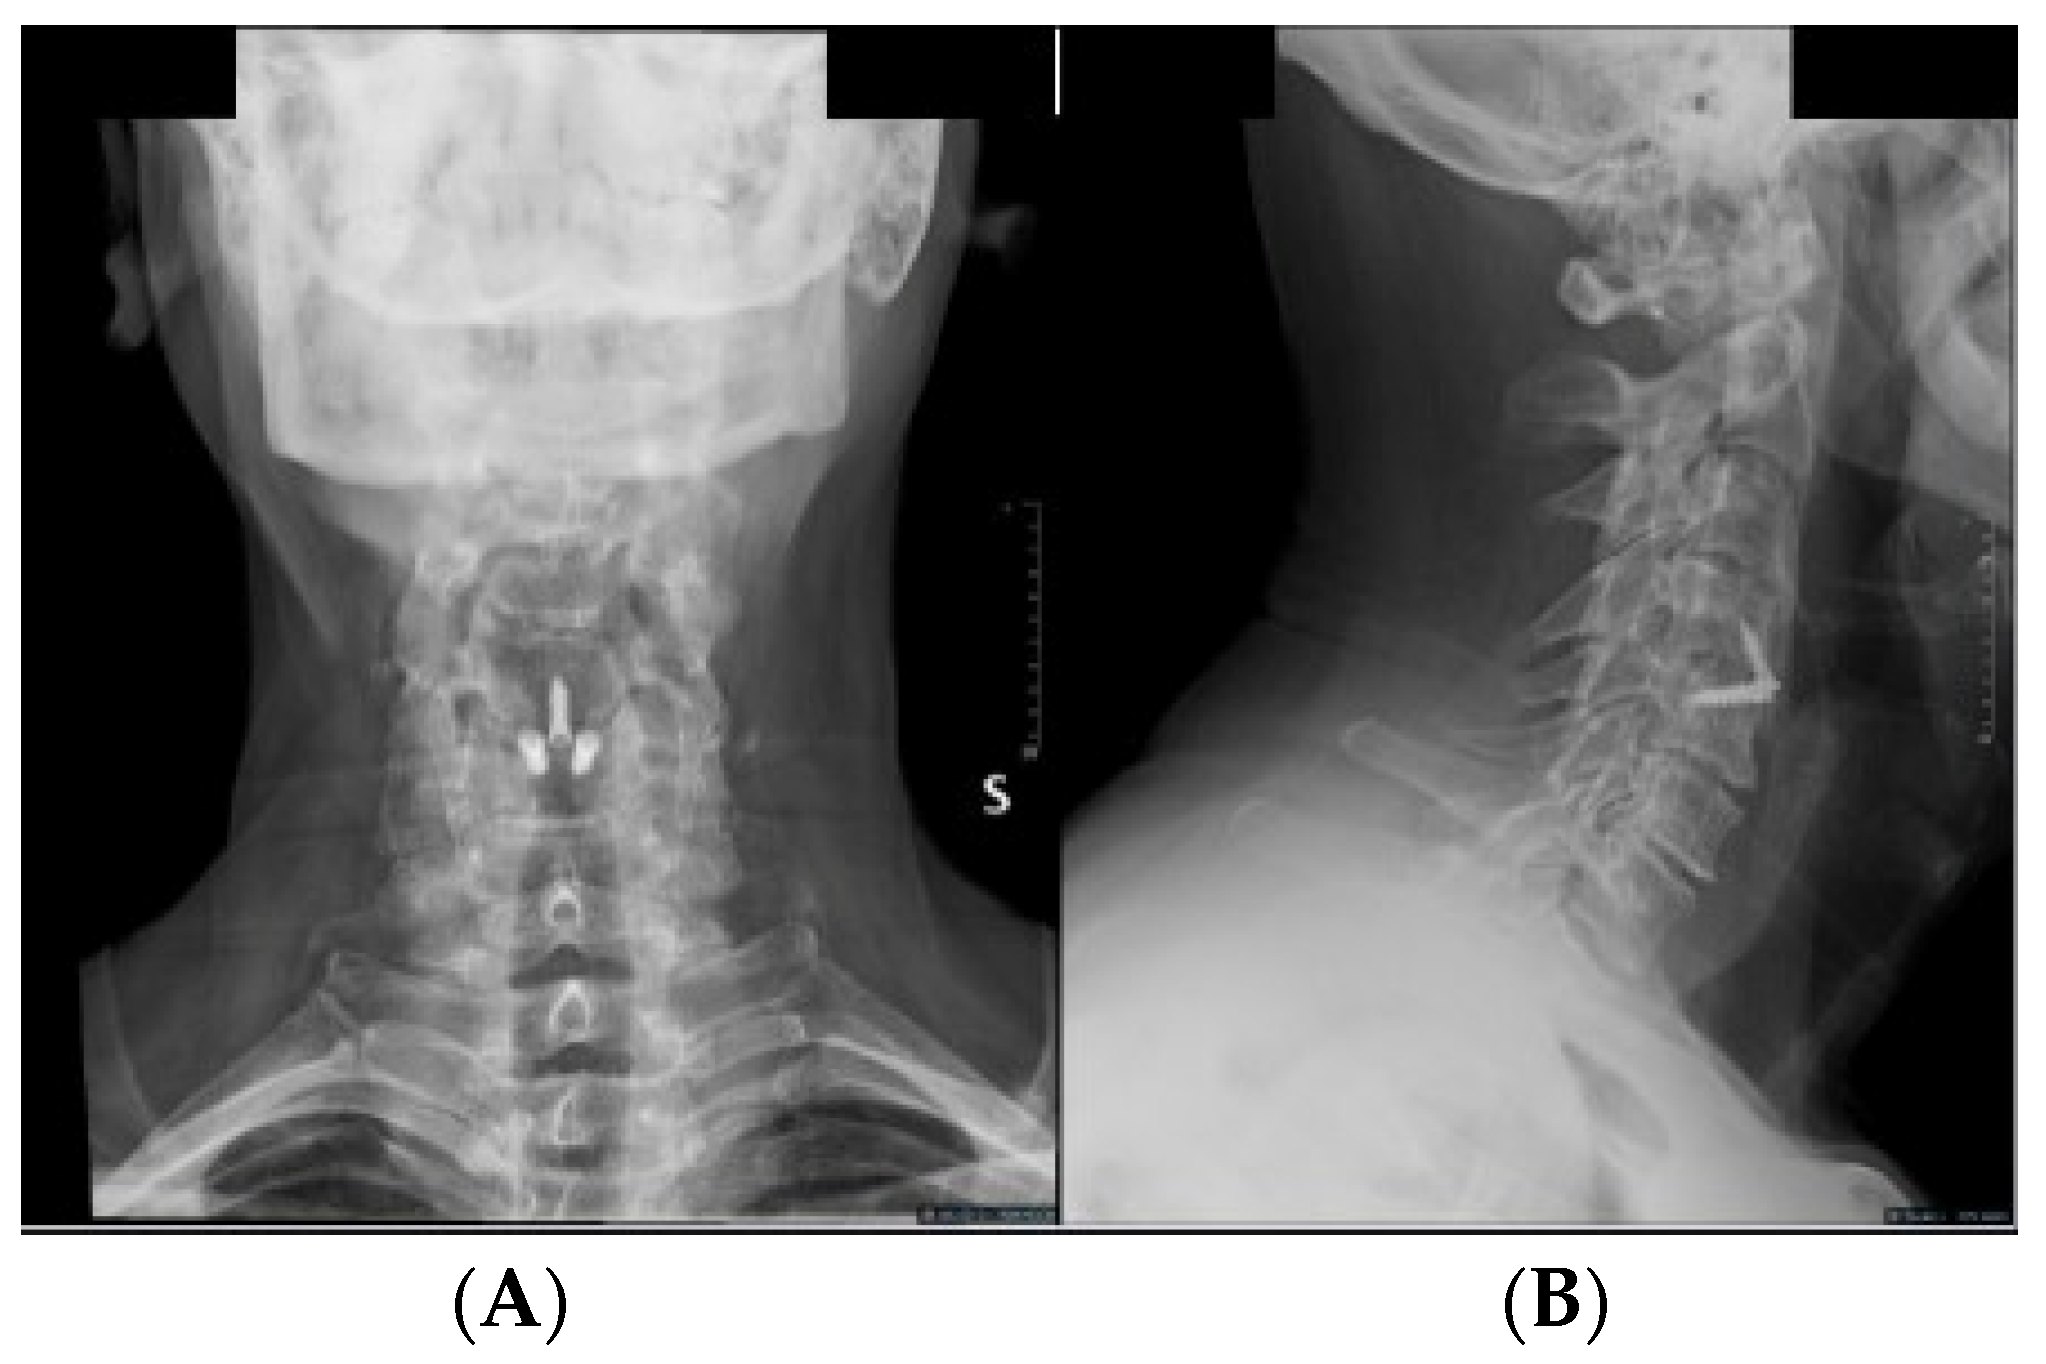

All procedures were performed by a senior experienced surgeon (G.S.). A standard anterior Cloward approach was employed [1], with Caspar distractors used as needed for vertebral body distraction. The discectomy and vertebral plate preparation were performed using high-speed drills and/or curettes, ensuring posterior longitudinal ligament opening and neural decompression. We used zero-P interlock PEEK cages with 7° lordosis, packed with a biphasic calcium–phosphate bone graft substitute (AttraXPutty®, NuVasive®, San Diego, CA, USA). Three screws anchored the cage, with two in the superior vertebral body and one in the inferior one at a 40° angle (Figure 1).

Figure 1.

Postoperative (A) AP and (B) lateral X-ray displaying a C4-5 ACDF using an interfixated zero-profile PEEK cage.